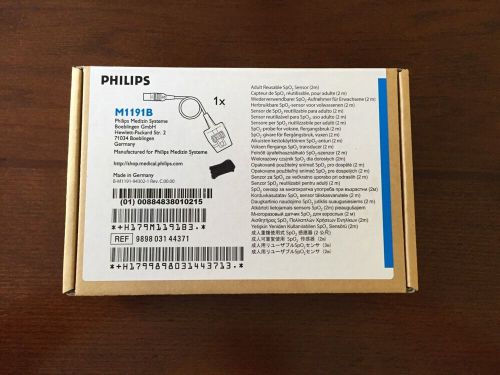

Philips Pulse Oximeter Sensor M1191B